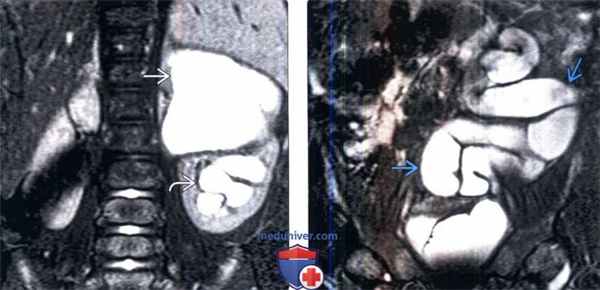

(Слева) МРТ, Т2-ВИ, корональный срез: удвоение левой собирательной системы с заметным гидронефрозом верхнего полюса и умеренным гидронефрозом нижнего полюса.

(Справа) МРТ, Т2-ВИ, корональный срез: у этого же пациента отмечается заметное расширение и извитость части эктопического мочеточника верхней лоханки.